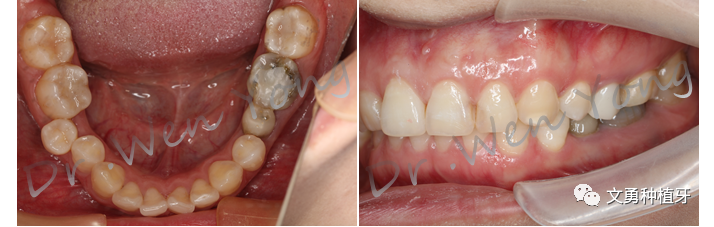

1、术前口内照片:75乳牙滞留

2、术前CBCT示:75根尖周低密度影,颊侧骨板完整